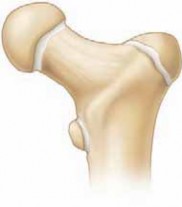

Chapter 10 Pediatric Hip Fractures R. Dale Blasier DEFINITION Hip fractures in children may be intra-articula…